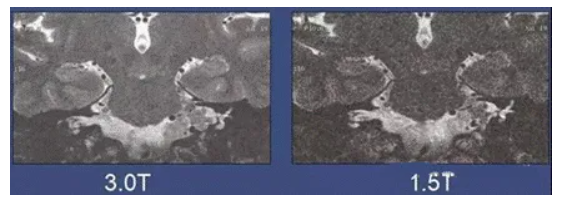

那1.5T和3.0T的设备,有什么区别呢?

一般来说,主磁体的磁场强度越高,扫描时间和图像质量越好。

具体而言:3.0T核磁共振相对于1.5T核磁共振,图像清晰度更高、扫描速度更快。3.0T拥有更高的磁场( 能够创建图像)和在较快扫描速度下获得清晰度更好的图像。然而,1.5T系统的扫描时间可能会比3.0T系统长的多。相反的,1.5T也可以缩短扫描时间,但图像质量就会有所牺牲。